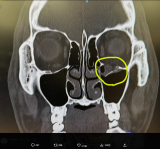

- YA-MANが公開したレントゲン。左目の下の骨がポッキリ折れている(@yaman_kosf)